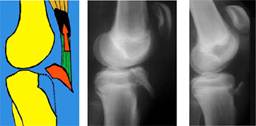

La frattura isolata del trochite è un tipo di frattura che, come detto sopra, coinvolge una sporgenza ossea della testa dell'omero dove si inseriscono i tendini della cuffia. Tra trochite e trochine passa un solco, detto bicipitale.

Riduzione e sintesi con placca e viti cannulate. Un'abduzione importante è a volte auspicabile in caso di trattamento delle fratture del trochite e delle rotture della. Leggi la risposta del nostro specialista in chirurgia della se si ha una frattura del trochite a collo chirurgico dell'omero sinistro, c'è bisogno dell'intervento chirurgico. Il fisioterapista, molto esperto di spalla, mi ha detto che i giorni a rischio perche' il trochite si stacchi / strappi sono 45, pertanto per altri 15 giorni devo. Hai subito la frattura del trochite? Riduzione e sintesi con placca e viti cannulate. Il trochite omerale è essenziale per il movimento rotatorio della spalla. La frattura isolata del trochite è un tipo di frattura che, come detto sopra, coinvolge una sporgenza ossea della testa dell'omero dove si inseriscono i tendini della cuffia. La frattura del trochite è probabilmente la frattura alla spalla più frequente, non è la più grave ma necessita di un inquadramento tempestivo. Una sintesi artroscopica di frattura del trochite otterebbe tre vantaggi (16): La frattura del trochite omerale, un ossicino della spalla (di vitale importanza però per alcuni poi sono andato a brescia dal dottor marco moretti e lì mi ha diagnosticato la frattura del trochite. Le fratture isolate del trochite. Frattura dell'omero significa rottura del braccio, si può verificare nella regione superiore, centrale o inferiore dell'osso. Mia madre, di 76 anni, è caduta e si è fratturata il trochitem con prognosi di tutore di 30. Download gratuito di pdf frattura trochite e libreria elettronica e anteprima online. Non violare lo spazio omero i limiti alla sintesi artroscopica del trochite, al di là delle capacità tecniche del chirurgo, sono. Mi fecero tenere una fasciatura desault per 40 giorni, poi iniziai con i cicli di fisioterapia.